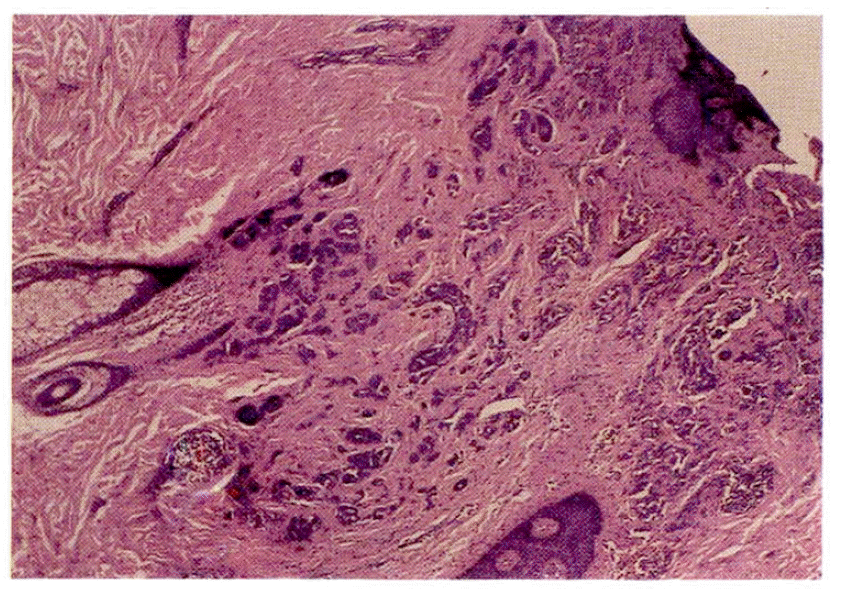

Five weeks before admission she began to cough up blood-streaked sputum. In a recumbent position she suffered from mild dyspnea and wheezing respiration intermittently. Ten days before admission she coughed up frank blood. At the time of admission, the physical examination revealed wheezing and decreased breath sounds in the left lower lung field. Mucocutaneous lesions and palpable lymph nodes were not present. Chest roentgenogram showed left lower lobe collaps (Fig. 2). Laboratory data were normal except for lactic dehydrogenase (LDH) of 414 IU/L. Liver scan was normal. Four repeated sputum cytologic examinations were negative for malignant cells. Pulmonary function tests showed a moderate restrictive pattern. On bronchoscopy, a fungating, dark grayish, irregularly surfaced endobronchial mass at the orifice of the left lower lobe bronchus nearly completely occluding the lumen (Fig. 3) was found. Bronchoscopic biopsy revealed metastatic malignant melanoma (Fig. 4). Computed tomography of the chest showed left lower lobe collapse and aortic invasion (Fig. 5). So palliative chemotherapy with dimethyl triazeno imidazole carboxamide (DTIC) was given as a five day schedule and she was discharged.